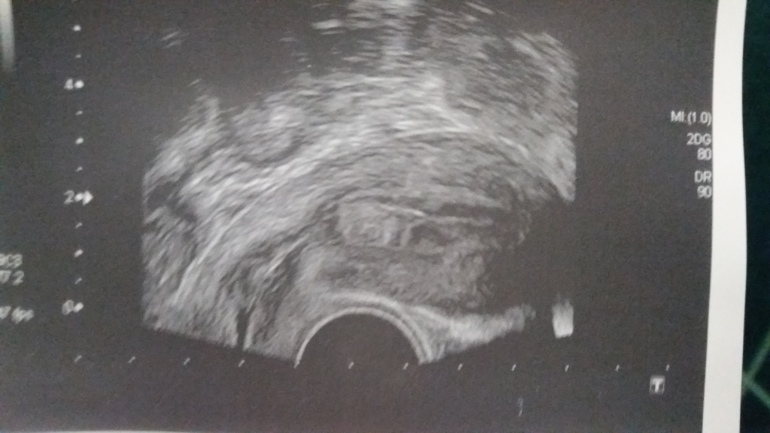

Фолликулометрия Резерв яйцеклеток